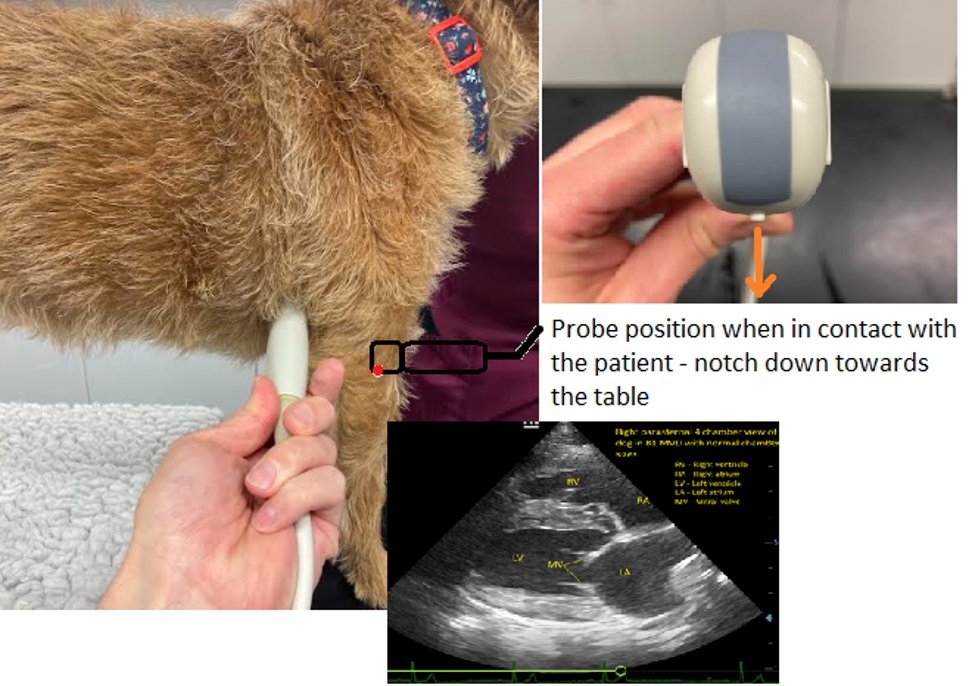

Obtaining the right parasternal 4 chamber view:

· Select probe and cardiac settings if available. Whilst a phased array probe is best for echocardiography a microconvex probe will work fine for POCUS

· Be aware of the probe orientation marker. This will help to orient you during scanning. For scanning the author prefers to have this marker on the left of the screen (see below image)

With the patient standing or in sternal (preferable over recumbency for the dyspnoeic/stressed patient), feel for the apex beat of the heart in the right axilla.

Place the probe on the chest in this location in the intercostal space, marker down towards the table/nearest the sternum

· Keep the probe perpendicular to the chest wall for this view

· Make very slight probe adjustments to achieve the 4 chamber view

· If the image is tilted, moving slightly up the chest wall away from the sternum can make the image more horizontal